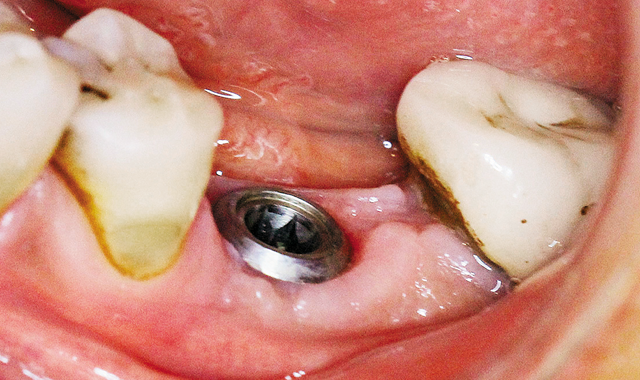

Fig. 9 Six weeks later.

Six weeks later, an impression was taken (Fig. 9, above; Figs 10-12, below).

Fig. 10 After removing healing cap.